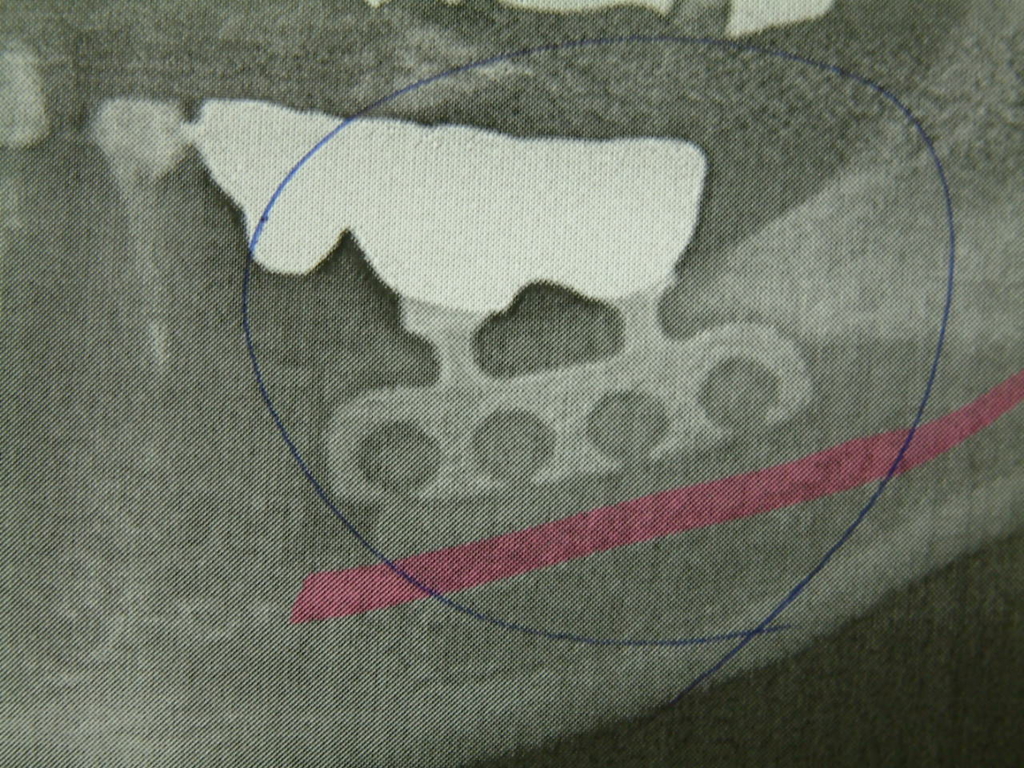

「かなり初期のインプラントですね。インプラントの上から歯周病菌が侵入して骨の一部が溶けてしまっています。」

刈総の先生はそう説明し入院手術を希望するか日帰り手術を希望するか尋ねた。